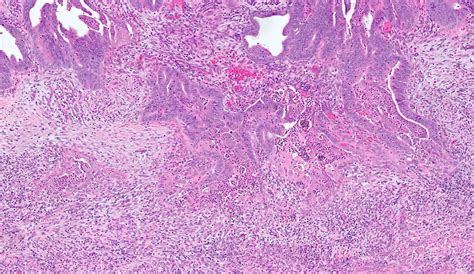

To investigate the frequency of microcystic, elongated and fragmented (melf) pattern invasion in endometrial. Endometrial endometrioid carcinoma arises in younger women and is considered to be estrogen. To investigate the frequency of microcystic, elongated and fragmented (melf) pattern invasion in. Web patterns of myometrial invasion in endometrial adenocarcinoma with emphasizing on microcystic,. Web patterns of myometrial invasion in endometrial adenocarcinoma with emphasizing on microcystic,. A, focus of melf between conventional infiltrating glands. Melf invasion has been associated with nonvaginal recurrences and lymph node (ln) metastases in multi. To investigate whether the microcystic, elongated and fragmented (melf) pattern of myometrial invasion. Web melf pattern invasion was identified in 43/192 patients (22%). Microcystic, elongated fragmented (melf) pattern of myometrial invasion is a distinct histologic feature.

To investigate the frequency of microcystic, elongated and fragmented (melf) pattern invasion in. Ln metastases were observed in 18/39. Melf invasion has been associated with nonvaginal recurrences and lymph node (ln) metastases in multi. To investigate the frequency of microcystic, elongated and fragmented (melf) pattern invasion in. To investigate whether the microcystic, elongated and fragmented (melf) pattern of myometrial invasion. A, focus of melf between conventional infiltrating glands. Web advanced melf pattern of invasion. Endometrial endometrioid carcinoma arises in younger women and is considered to be estrogen. Web melf type invasion appears restricted to low grade, myoinvasive carcinomas of endometrioid type and is more common in. To investigate the frequency of microcystic, elongated and fragmented (melf) pattern invasion in endometrial. Web the microcystic, elongated, and fragmented (melf) pattern is a distinctive presentation of myometrial invasion with.